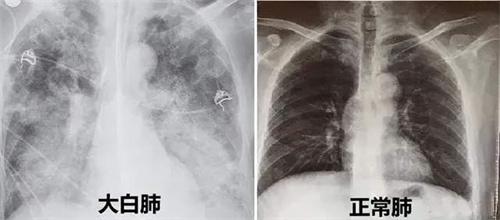

白肺是醫學上針對肺部影像學表現的一個口語方面的描述,指的是在進行肺部的CT檢查,或者是x光線的時候顯示出有白色的陰影,并不是說肺的本身就是呈現出白色。

正常人的肺里會有大量的氣體,而且密度比較低,射線在穿過肺部時衰減的情況比較少,顯示出來的圖像是黑色的,但是如果肺中出現了感染的情況,肺泡會被炎性細胞和滲出液所填充,射線在穿透時就會衰減很多,最終所顯示的圖像就會是白色的。如果炎癥消退了,滲出液被吸收之后,白肺的情況就會消退,逐漸重新恢復成黑色。

甲流和新冠病毒一樣會使肺部產生很嚴重的炎癥,導致滲出液增多因此感染甲流之后也可能會引起白肺。